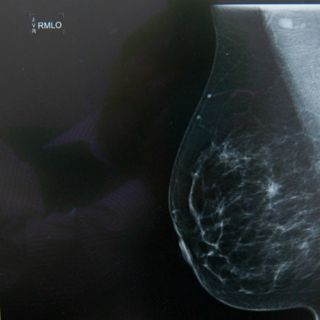

El académico describió que el método más utilizado para la detección de cáncer de mama es la mamografía, radiación que arroja una imagen anatómica del seno mediante la cual se pueden observar formaciones atípicas en el tejido.

"La mamografía es un estudio anatómico, mientras que la termografía infrarroja es un análisis funcional del seno. La unión de las partes anatómica y funcional es la que daría un mejor diagnóstico", apuntó.